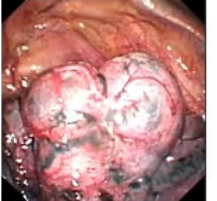

近年来,贵州航天医院各科室紧跟医学前沿,不断强技术、补短板,大力开展新技术、新项目,完成了许多高精尖、高难度、本地区“首例”的技术,填补了医院医疗技术空白,满足了群众日益增长的医疗需求。 贵州航天医院呼吸与危重症医学科是贵州省内呼吸疾病治疗规模最大,诊疗项目最全的呼吸疾病品牌科室,呼吸介入技术达到了全国先进水平,在贵州省内处于领先的地位。 本期,我们将为大家带来呼吸与危重症医学科特色技术——内科胸腔镜技术诊断和治疗胸腔疾病。 案例分享 患者苟某某,因劳累、气促,不明原因胸腔积液在某县一医院采取反复抽水等治疗手段效果不佳,当地医院考虑到患者年龄大(77岁),基础疾病较多,病情复杂,结合当地诊疗水平能力情况,建议转到上一级医院诊治,通过我院与该院建立的呼吸专科联盟绿色通道转入了我院。 患者入院后,呼吸与危重症医学科第一时间复查胸部CT,提示:右肺中叶、左肺感染,纤维化灶,左侧中量胸腔积液,右后侧胸膜轻度增厚,心包少量积液;并完善心电图、血常规、凝血功能、生化指标等术前检查。经科室专家团队集体讨论,得出患者左侧胸腔积液可能原因:结核?恶性?其他?冠心病、心功能不全、高血压病3级(高危组)、陈旧性肺结核复发?肺部感染;为进一步明确诊断,在充分评估、做好术前准备及应急预案、与患者及家属沟通的情况下,决定为患者进行内科胸腔镜检查术。 科室在患者入院第3天便实施了内科胸腔镜检查术,经检查取活检,病理不排除胸膜间皮瘤,送遵义医科大学附属医院病理会诊后诊断:胸膜间皮瘤。明确诊断后,科室专家团队为患者制定了个体化的治疗方案,患者病情很快得到有效控制,最终满意出院。半年后,医院通过电话回访,患者病情稳定,生活质量明显改善。 什么是内科胸腔镜 内科胸腔镜(medical thoracoscopy,MT)是一项微创诊断和治疗胸腔疾病的重要技术。主要应用于无创方法不能确诊的胸腔积液和胸膜疾病,通过局部麻醉后在胸壁做一个小切口,插入胸腔镜,直接观察胸膜、肺表面、纵隔等部位的病变情况,可进行活检、粘连松解及胸膜固定等操作。具有创伤小、恢复快、诊断准确性高等优点。 内科胸腔镜原理 内科胸腔镜是一项利用现代光学技术和成像技术的侵入性操作技术,应用电子支气管镜、硬质或软硬结合(半硬)的胸腔镜的一种电子内窥镜,末端装有连接着显示屏的微型摄像头。通过胸壁1-2cm左右的小切口,将内科胸腔镜及专用器械(戳卡套管)通过小切口进入胸腔,微型摄像头将胸腔内的情况投射到显示屏幕上,医生可以通过镜头全面、直观地观察患者胸腔内情况,了解胸膜病变确切位置和形态改变,还可对胸膜上的病变进行活检及治疗的操作技术,安全、微创、几乎无痛地“揭秘”不明原因的胸腔积液。 内科胸腔镜技术优势 (一)安全性高:仅需局部浸润麻醉,并发症发生率相对较低,对患者的身体条件要求较低。 (二)操作简便:操作时间短,痛苦少,患者耐受好。 (三)微创性:切口小,对患者身体损伤小,术后疼痛轻,恢复快。 (四)高分辨率成像:清晰显示胸腔内细微病变,提高诊断准确性。 (五)可直视操作:直接观察病变,进行精准活检和治疗。 (六)适用范围广:可用于不明原因胸腔积液、胸膜疾病、肺部疾病等的诊断和治疗。 (七)费用低:与外科胸腔镜比较费用低廉。 内科胸腔镜技术是贵州航天医院呼吸专科和呼吸介入诊疗优势的一部分,在2016年率先开展了内科胸腔镜技术,年手术量约100余例,已建立了快速、精准、规范、有效的一体化诊疗服务体系。目前呼吸与危重症医学科内科胸腔镜技术广泛应用于不明原因胸腔积液、气胸、脓胸的诊断和肺癌、弥漫性恶性胸膜间皮瘤等的分期,恶性或复发性胸腔积液、早期脓胸、自发性顽固性气胸的治疗。 镜下常见表现:单发或多发结节、灰白色弥漫性粟粒样结节、胸膜充血、水肿、胸膜增厚及纤维分隔或粘连带形成。 诊断方面: 胸腔积液的病因诊断。内科胸腔镜对恶性胸腔积液的诊断率可高达90%以上,胸腔镜对结核性病变诊断率极高,几乎达到96%以上。 腺 癌 恶性淋巴瘤 软骨肉瘤胸膜转移 滑膜肉瘤胸膜转移 结核性胸膜炎 治疗方面: 脓胸 肺大泡 贵州航天医院 呼吸与危重症医学科学科带头人 廖江荣 国务院政府特殊津贴专家 二级教授 主任医师 贵州航天医院副院长 国家级学术任职: 第二届中国医药教育协会介入微创专业委员会呼吸分会副主任委员 中国抗癌协会肿瘤微创治疗专业委员会常务委员 中国防痨协会结核病转化医学专业分会常务委员 第一届中国人体健康科技促进会呼吸介入专委会常务委员 中国医疗保健国际交流促进会结核病学分会第三届委员会常务委员 中国抗癌协会肿瘤微创治疗专业委员会粒子治疗学组第四届委员会委员 中华医学会结核临床专业委员会内镜介入委员 中华医学会放射学分会第十五届委员会介入学组呼吸系统介入专业委员会委员 北京健康促进会中青年专家委员会胸部疾病精准活检分委会副主任委员 中国医师协会介入医师分会第二届委员会肿瘤消融专业委员会委员 中国结核病防治综合质量控制专家指导委员会委员 亚洲冷冻治疗学会常务委员 世界内镜医师协会呼吸内镜协会常务理事 内镜临床诊疗质量评价专家委员会委员 “西部呼吸介入联盟”副理事长 专业擅长: 贵州航天医院 呼吸与危重症医学科简介 贵州航天医院呼吸与危重症医学科以呼吸危重症和介入呼吸病学为强力推手,以肺部感染性疾病及肺癌、肺小结节的早期精准诊疗、慢性呼吸疾病康复治疗为特色,以人才团队建设为核心的科室发展模式,现已成为省内呼吸疾病治疗规模最大,诊疗项目最全的呼吸疾病品牌科室。是贵州省医学重点学科、临床医学重点专科建设单位,遵义市首批呼吸重点学科、重点专科建设单位。是国家卫健委能力建设和继续教育肿瘤微创介入建设中心、贵州省县级医院微创介入培训中心、遵义市呼吸疾病临床医学中心。是国家呼吸医疗质量控制与管理哨点医院、遵义市呼吸内科专业医疗质量控制中心。是中国医药教育协会介入微创呼吸分会呼吸介入技术培训中心单位;国家卫健委海医会呼吸分会ROSE专委会“诊断性介入肺脏病学快速现场评价”培训基地;中国肺癌防治联盟“贵州航天医院肺结节诊治”分中心,中国人体健康科技促进会呼吸介入技术培训基地,贵州省中西医结合会呼吸学分会呼吸介入专委会主委单位。 基本情况 平均每年开展气管镜诊疗约4000例,经皮肺穿刺介入诊疗近千例,开展的项目包括经支气管镜(软、硬)下冷冻、氩气刀、高频电刀、球囊扩张、支架置入、超声内镜诊疗等气道介入诊疗技术,经皮肺穿刺活检及肿瘤消融术(微波、冷冻)、ROSE技术、内科胸腔镜诊疗及经血管介入诊疗技术,且多项呼吸介入诊疗技术在省内处于领先水平。 诊疗范围 航天医院呼吸专科擅长:致力于呼吸系统感染性、疑难性疾病的介入快速精准诊疗;肺癌与肺小结节早期精准诊疗水平项目提升。擅长于呼吸系统(肺)疑难病的诊断及危重病的救治,尤其在肺癌、肺小结节的早期诊断;肺癌综合靶向治疗;肺结核综合诊疗;肺部疾病的介入诊疗在省内处于前沿水平。 咨询热线 (一)呼吸与危重症医学科一病区 医生办公室:27677317 护士站:28614217 (二)呼吸与危重症医学科二病区 医生办公室:28691274 护士站:28690442 (三)呼吸与危重症医学科三病区 医生办公室:28692417 护士站:28690461 (四)呼吸与危重症医学科四病区 医生办公室:28616402、27677582 护士站:28614987、27677862